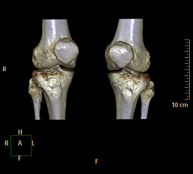

- TC Rodillas Exploración radiológica que mediante un sistema de rayos X y detectores que giran alrededor del paciente, reconstruyendo las imágenes por ordenador (TC Multidetector), permite el estudio de huesos, músculos y articulaciones de la rodilla. Exploración radiológica que mediante un sistema de rayos X y detectores que giran alrededor del paciente, reconstruyendo las imágenes por ordenador (TC Multidetector), permite el estudio de huesos, músculos y articulaciones de la rodilla.